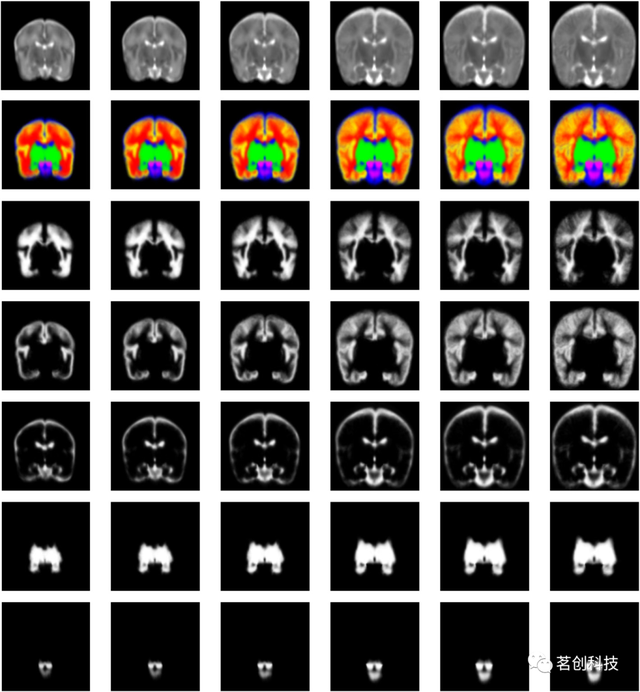

发育中大脑的动态4D概率图谱

这是一组矫正胎龄后的29-44周新生儿的概率图谱,由153名不同年龄的新生儿受试者细分而来。该图谱由平均T2加权强度模板和相应的组织概率图组成,具有动态生成结构的矫正尺寸和形状。该图谱提供了六种结构的组织概率图——皮层、白质、皮层下灰质、脑脊液、脑干和小脑。组织细分是基于皮层下灰质、脑干和小脑的分割,这是通过对三个典型图像的手动分割转换为其他图像得到的。

来源:A dynamic 4D probabilistic atlas of the developing brain.

高分辨率的新生儿大脑时空图谱

该图谱是胎儿图谱“发育中胎儿大脑的多通道4D概率图谱”的扩展,用于扫描矫正胎龄后28至44周的新生儿大脑。该图谱由来自204名早产新生儿的组平均T1和T2加权MRI模板组成。生成的4D图谱很好地反映了大脑整体和局部的变化。该模板还包括发育中大脑的87个标记结构。使用ALBERT多图谱作为先验知识用于图像分割。

Regional growth and atlasing of the developing human brain.

UNC婴儿0-1-2图谱

这是一套针对新生儿、一岁和两岁婴幼儿的纵向时空图谱,共95名。这些新生儿在出生后五周内进行了首次扫描,并在一岁和两岁时进行了纵向扫描。这种纵向设计是避免选择偏差的一个重要特征,这在横截面设计中是不可避免的。该图谱由组平均T1和T2加权图像组成,其中包括灰质、白质和脑脊液的组织概率图,这些图像是使用应用于每张图像的自动图像分割方法创建的。该图集还包含从自动解剖标记(AAL)传播的分割图谱。

来源:Infant brain atlases from neonates to 1- and 2-year-olds.

UNC纵向0-3-6-9-12个月大的婴儿图谱

这是一组典型的0、3、6、9和12个月大的婴儿时空图谱,由35名健康婴儿组成,这些婴儿每三个月进行一次纵向扫描,直到一岁。该图谱由组平均T1和T2加权图像组成,其中包括灰质、白质和脑脊液的组织概率图。其主要意义在于同时引入了时间和空间约束,以生成具有丰富结构细节和纵向一致性的图集。纳入了3个月、6个月和9个月的图谱有助于分析婴儿MRI,因为在生命的第一年,大多数大脑区域的灰质和白质之间的T1和T2加权对比度仍然很差。

来源:Consistent spatial-temporal longitudinal atlas construction for developing infant brains.